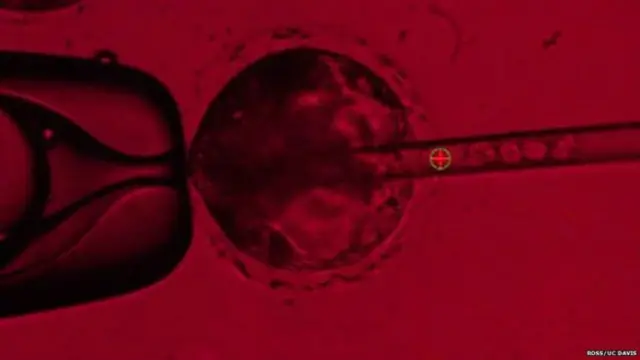

Domuz embriyolarına enjekte edilen kök hücreler ile "chimera" olarak bilinen insan-domuz melezi embriyoları geliştirilme çalışmaları başlatıldı.

Chimera embriyolarının geliştirilmesi iki aşamada oluyor.

- İlk olarak CRISPR olarak bilinen bir genetik değiştirme yöntemiyle yeni oluşan bir domuz embriyosunun DNA'sı ayrıştırılıyor.

- Sonra da embriyoda oluşan boşluğa gen manipülasyonu yöntemiyle "iPS" denilen hücreler yerleştiriliyor.

Kaynak, RossUC Davis

Yetişkin bir insandan alınan iPS hücreleri manipüle edilerek kök hücreye dönüştürülüyor ve böylece domuzun vücudunda herhangi bir organa dönüştürülme potansiyeline kavuşuyor.

Bu insan kök hücrelerinin domuz embriyosundaki boşluktan faydalanarak embriyonun insan pankreası oluşturması bekleniyor.